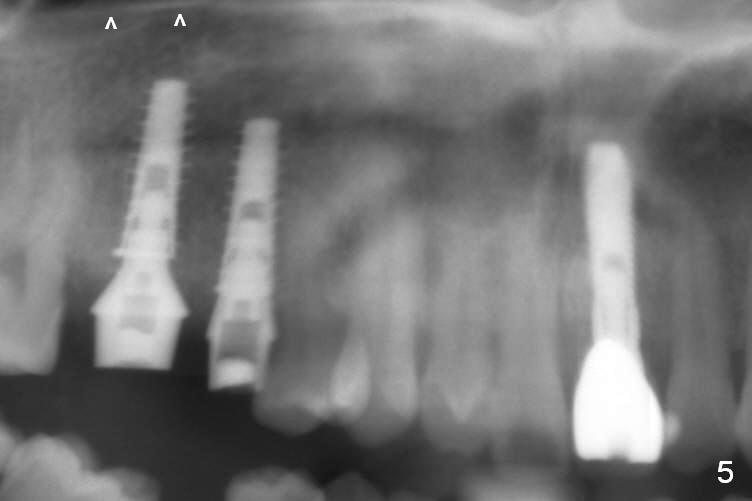

After extraction, osteotomy is established in the septum of #3 and the mesial slope of the shallow socket of #4 (Fig.2 red dashed line) for 11 and 13 mm deep, respectively. Since the septum is sloped palatally, a series of Magic Drills (MD) are used. A single large MD may wobble in the slope. By the time MD 3.8 mm is used, there is perforation palatally. The insertion torque of 4.5x13 mm IBS implant is less than 30 Ncm (Fig.3). In retrospectively, the osteotomy should have been initiated more buccally or deeper, since there is fair amount of clearance from the sinus floor (Fig.5 ^). The implant at #9 is 3.8x16 mm.